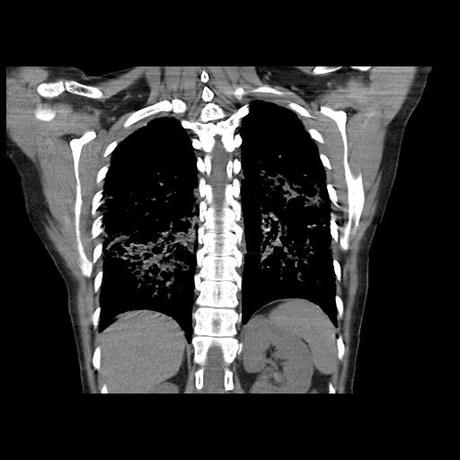

Se realiza volumen de tórax en fase simple, desde los opérculos torácicos hasta los hemidiafragmas, observándose:

El parénquima pulmonar con areas parcheadas difusas en vidrio despulido combinadas con otras areas hipodensas de baja atenuación debidas a atrapamiento aéreo y engrosamiento intersticial y zonas de fibrosis de predominio en lóbulos medios e inferiores de ambos pulmones.

- LOS HALLAZGOS PUEDEN ESTAR EN RELACIÓN A NEUMOPATIA INTERSTICIAL PROBABLE ETIOLOGIA HIPERSENSITIVA VS AUTOINMUNE/BACTERIANA/FUNGICA.